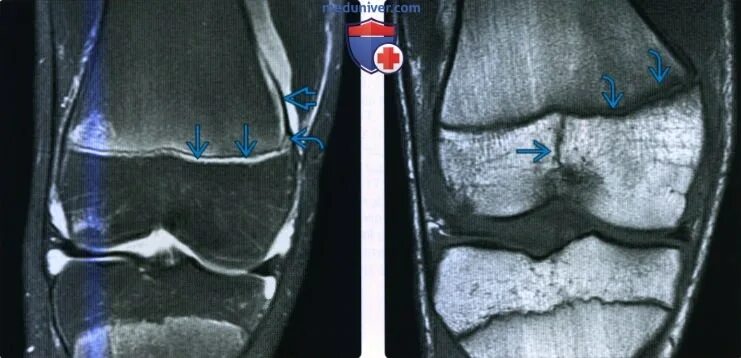

Перелом мрт или кт